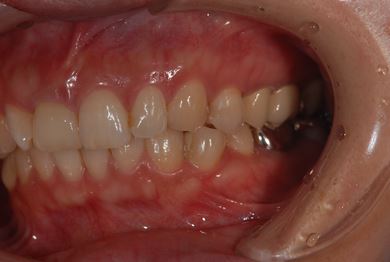

| 性別/年齢 | 女性 / 38歳 | ||||||||||||||||||||||||||||||||

| 主訴 | 右奥歯2本、インレーの相談をしたい。 | ||||||||||||||||||||||||||||||||

| 治療方針 | セラミック治療にて、審美的回復を行う。 | ||||||||||||||||||||||||||||||||

| 治療内容 | ハイブリッドセラミックインレー2本、メタルボンドセラミッククラウン2本(メタルボンド用土台2本)、オールセラミッククラウン1本(オールセラミック用土台1本) | ||||||||||||||||||||||||||||||||